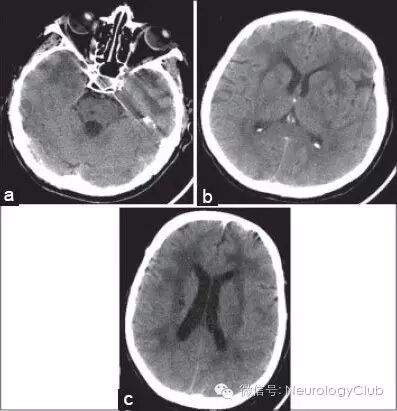

(图6:A:颞极低密度病灶级脑桥腔隙性梗死;B:脑室旁低密度病灶,累及外囊;C:白质弥漫低密度,基底节区可见腔隙性梗死)

(图8:A-B:FLAIR上可见皮质-皮质下交界处多发低信号病灶[箭],为与血管周围间隙扩张有关的腔隙。这些病灶为CADASIL较为特异的影像学表现,见于约67%的患者,常伴有前颞叶融合的白质高信号)